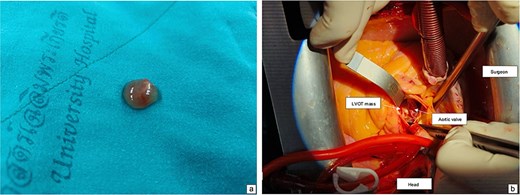

A histological view of the excised mass reveals elongated and branching papillary fronds with central avascular collagen, lined by hyperplastic epithelial cells.

The patient underwent surgical excision of the LVOT mass via a median sternotomy. Cardiopulmonary bypass (CBP) was established using arterial cannulation in the ascending aorta and single, two-stage venous cannulation via the right atrium. An oblique aortotomy was performed to access the LVOT, and the mass was completely excised. The aorta was closed with 4–0 Prolene, and the excision site was inspected to ensure no residual tissue. Hemostasis was achieved, and CBP was weaned off once adequate cardiac function was confirmed. Two tube drainages in pericardial and mediastinal spaces. The pericardium was closed, with a total CBP time of 45 min, an aortic cross-clamp time of 27 min, and a total operative time of 3 h and 12 min. Gross pathology showed a 1 × 1 × 0.3 cm irregular, soft, grey-white polypoid mass. Histology examination of the mass revealed multiple branching papillary fronds with a central avascular collagen, lined by a layer of hyperplastic epithelial cells, consistent with papillary fibroelastoma (Figs 3 and 4).